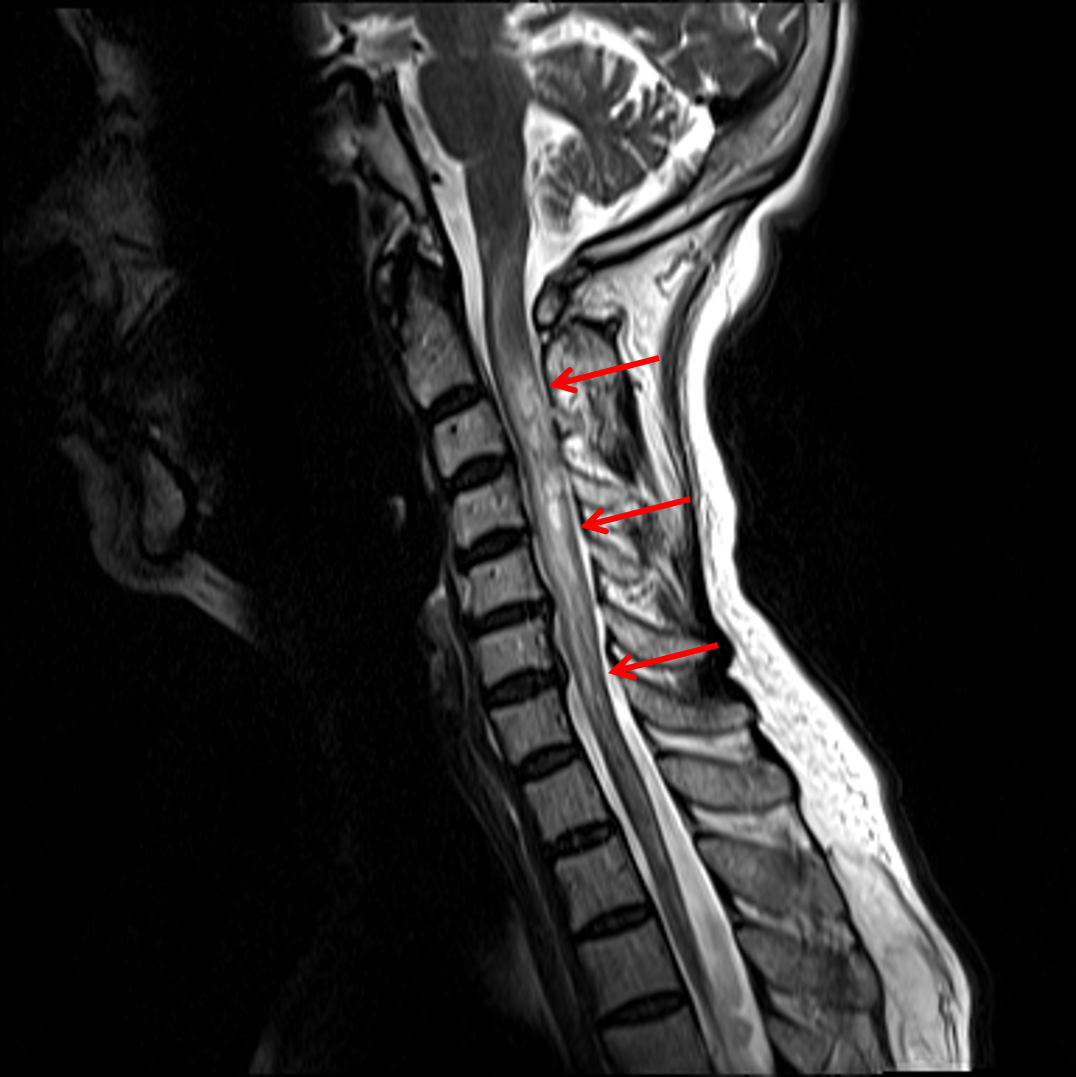

Transverse Myelitis Mrt - Diagnostischer Weg bei akuter Myelopathie unter besonderer ... : It is an inflammatory disorder of the spinal cord.. Webmd explains transverse myelitis, a condition that happens when your body attacks your transverse myelitis is an inflammation of your spinal cord. Transverse myelitis is a neurological disorder caused by inflammation of the spinal cord. Transverse myelitis interrupts the messages that the spinal cord nerves send throughout the body. It is an inflammatory disorder of the spinal cord. Transverse myelitis (in latin nomenclature:

Klinische eigenschaften von tm transverse myelitis (tm) ist ein akuter entzündlicher prozess, der einen fokalen herd im rückenmark betrifft. Acute partial transverse myelitis (aptm) is acute or subacute spinal cord inflammation involving only a portion of the spinal cord, but multiple definitions may be used, including the following. Transverse myelitis is an inflammation of both sides of one section of the spinal cord. Myelitis transversa) is a neurological disorder caused by an inflammatory process of the spinal cord, and can cause axonal demyelination. Partial transverse myelitis and partial myelitis are terms sometimes used to specify inflammation that only.

Transverse myelitis (tm) is an inflammatory disorder of the spinal cord that may be idiopathic or. Transverse myelitis is inflammation of one part of the spinal cord. Transverse myelitis is an inflammation of the spinal cord, a major part of the central nervous system. We can break down this disease state to better understand it: Myelitis transversa) is a neurological disorder caused by an inflammatory process of the spinal cord, and can cause axonal demyelination. Transverse myelitis is a neurological disorder caused by an inflammatory process of the gray and white matter of the spinal cord, and can cause axonal. The differential diagnosis of acute inammatory transverse myelitis (atm) is broad. What research is being done?

Transverse implies that the inflammation extends horizontally across the spinal cord.

Therefore, physicians must be aware of the many potential etiologies for acute myelopathy, and should pursue. This can cause pain, muscle weakness, paralysis, sensory problems, or bladder and bowel dysfunction. Myelitis transversa) is a neurological disorder caused by an inflammatory process of the spinal cord, and can cause axonal demyelination. Webmd explains transverse myelitis, a condition that happens when your body attacks your transverse myelitis is an inflammation of your spinal cord. Transverse myelitis is an inflammation of both sides of one section of the spinal cord. Transverse myelitis is a neurological disorder caused by an inflammatory process of the gray and white matter of the spinal cord, and can cause axonal. Acute partial transverse myelitis (aptm) is acute or subacute spinal cord inflammation involving only a portion of the spinal cord, but multiple definitions may be used, including the following. We can break down this disease state to better understand it: Transverse myelitis (tm) is a rare neurological syndrome. Transverse myelitis is an inflammation of the spinal cord, the part of the central nervous system that sends impulses from the. Transverse myelitis is a neurological disorder caused by inflammation of the spinal cord. This neurological disorder often damages the insulating material covering nerve cell fibers (myelin). The cause of 60% of tm cases may remain unknown despite the presence of.